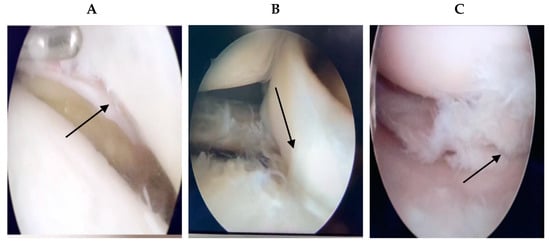

Figure 3. The intraoperative arthroscopic images of meniscus injury. Intraoperative diagnosis was made according to the arthroscopy of knee joint. The arrows point to the meniscus injury.

Patients who underwent surgery in our hospital and healthy patients who underwent MRI screening at our hospital were included. As there was no standard format for all MRI patient data, we selected the knee MRIs of 2000 patients from 2015 to 2021, excluding pixels that were too blurry to detect and patients with knee ligament injuries or other disorders. A total of 1396 knee MRI pictures were acquired, 716 of which were normal (Figure 2). For the remaining 680 pieces depicting meniscus injury, the age range was between 17 and 62 years (17–62 years). For all patients with meniscus injury in our hospital, the chief physician performed arthroscopic surgery, and the intraoperative diagnosis was the same as the MRI diagnosis of the radiologists. If a problem of knee joint meniscus and clean-up resection occurred, meniscus stitches were used. Figure 3 shows the intraoperative arthroscopic images of meniscus injury (Figure 3).